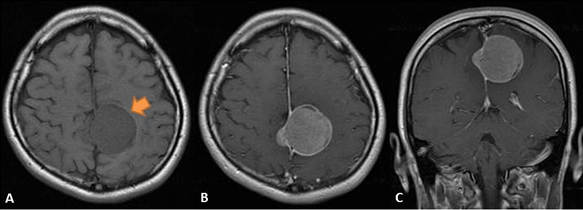

一つの可能性としては"脳腫瘍"だね

著しい人格変化を来たし、抑制が効かなくなると大変なことになる

多くは取り切れるタイプ(写真参照)だから死ぬ必要はないけど